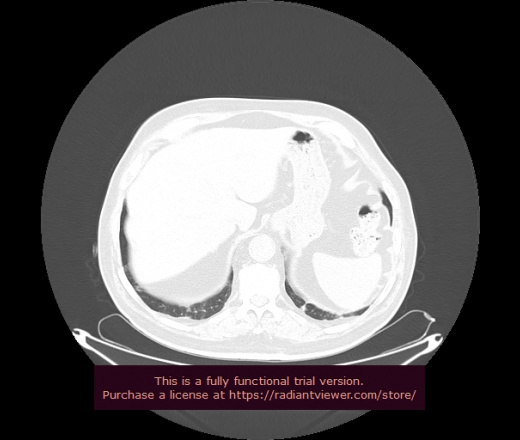

Уважаемые коллеги, если имеется интерес, сможете ли Вы спрогнозировать дальнейшее +-одинаковое течение процесса у 4 данных разных пациентов? Зацепиться где-то можно очень просто, где-то нельзя.